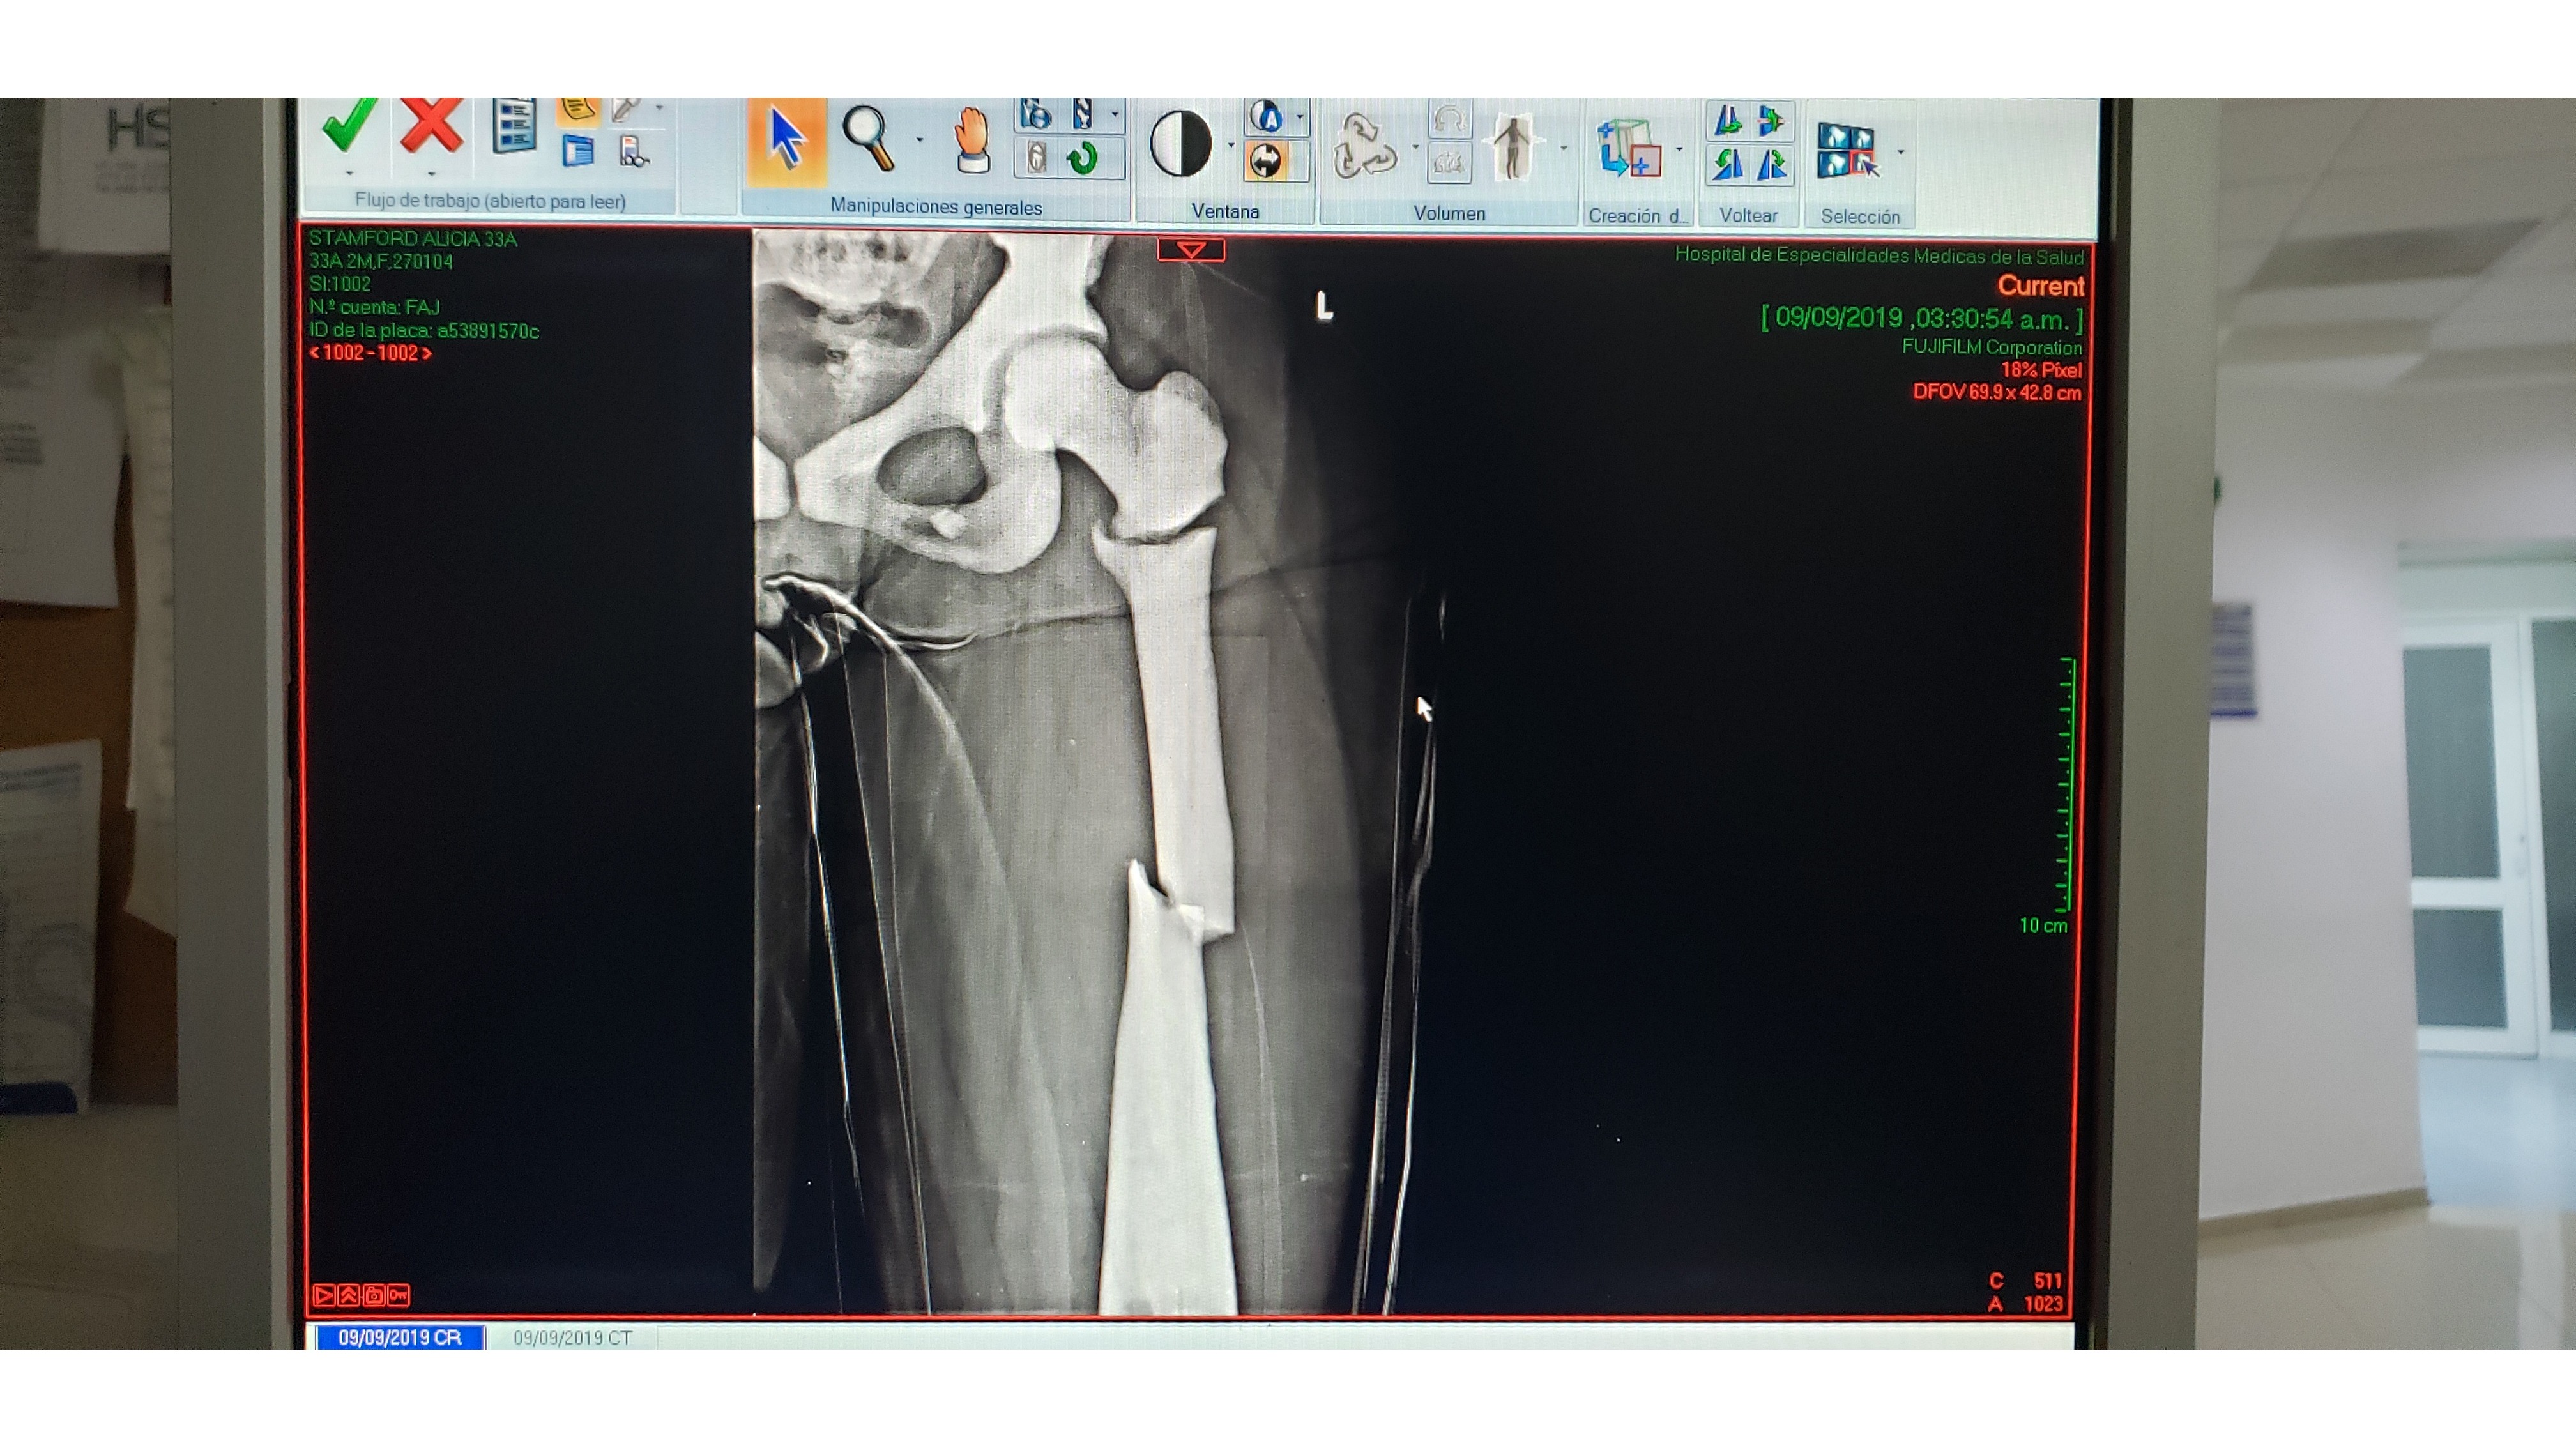

Please help me in supporting my dear friend Alicia who is currently going through the toughest time of her life, both physically and emotionally. ABOUT ALICIA Alicia is a 33 year old Australian, full of life and loves adventure. It had long been Alicia’s dream to travel overseas to Latin America. She saved for years, and set off in 2018. She fell in love with Mexico before she could move on to her next destination, and soon found her calling: to become a Divemaster or English teacher. Alicia fell off her bicycle last year and damaged her elbow, dashing her hopes of moving on to become a dive instructor. This was one of the worst hospital experiences she has ever had to endure, until last week. THE ACCIDENT Just over a week ago, Alicia was hiking with friends in the Sierra Alvarez in San Luis Potosí, in the centre of Mexico. Alicia had a bad fall and her leg and arm were pinned to the ground. The group was out of cell range and the guide had brought no first aid kit. She was made to believe there was nothing wrong and to move herself into sitting position and work her way out of shock. After two hours of trying to move her, the group dispersed to try to find help. They returned with a rescue crew 6 hours later, by this time it was dark and Alicia was beginning to suffer from, hypothermia and dehydration. The rescue team had to hike with Alicia tied to a table and transport her on the back of a truck on a 4x4 track then transfer her to an ambulance. To top if off, the ambulance had an accident by colliding with a tree trunk trying to get through the dark remote area, causing Alicia even more pain on the 2 hour drive back to the city. The rescue operation took 6 hours, all without anesthesia. THE HOSPITAL When she finally made it to the hospital, she was advised that she had fractured her femur in 3 places and had also fractured her upper arm on the opposite side. She woke up from her first operation to hear that it had been unsuccessful. She lost a lot of blood during the operation and we almost lost her. She was in ICU for several days. Upon waking from her second operation, Alicia was given the devastating news that her mother (who had been gravely ill) had passed away. The hospital had claimed they would work directly with her travel insurance at the beginning so they could admit her, and then took back their promise right before the operation. Every day whilst Alicia was in ICU, the hospital came collecting money, which Alicia's loving partner Chris had to borrow from everyone he knew to pay so they would not kick her onto the street. WHAT'S NEXT? We can only imagine the physical and emotional pain that Alicia has been going through – she has lost her independence, mobility and ability to make a living at the same time as she is grieving for the loss of her mother. She now faces an uphill battle – physically, emotionally and financially. Although she has now been released from hospital, Alicia will not be able to leave her bed for the next 2 months whilst her leg heals. She is unable to move independently and is fully reliant on help to feed, dress and shower her. Luckily, she is being cared for by Chris and his family. Once the two months are up, she has to leave Mexico and return Australia as soon as she is able to complete her medical recovery there. Alicia will have to return to Australia without her partner with no idea of if he will be able to join her in the future. She faces an uncertain future and has no idea when she will be able to work to support herself again. What's worse, she now no longer has the support of her mother to help her through this time. HOW YOU CAN HELP On her return to Australia, she will have to start afresh and will need funds to help support herself until she is well enough to find work again. She will need months of physiotherapy and counselling, lots of medications which all add up, plus taxis to get to all of her medical appointments, plus food and rent whilst she is not working. I know that Alicia is extremely uncomfortable about asking for financial help, but I asked her to swallow her pride. When bad things happen to other people, we often ask ‘what can we do to help?’ It’s especially hard to feel useful when someone is suffering miles away on the other side of the world. Making a small donation to help Alicia get through these next months would mean the world to her. She is going to have a tough enough time getting through the physical pain she is experiencing, let alone the grief she is feeling for having lost her mother, the sadness she feels at having to leave Chris and Mexico, and her uncertainty about her future in Australia. Being so far away, we can't offer her any physical help, but it doesn't take much to pull a credit card and give a few dollars, those dollars will mean more to her than whatever you may spend it on later this week. This is ‘what you can do to help’ to show Alicia that you support and love her during this extremely difficult time. Thank you xx Image 1: Alicia on her travels Image 2: The last time Alicia saw her mother, saying goodbye in Australia. Image 3: Alicia with her loving partner Chris, who unfortunately can't join her in Australia for financial reasons. Image 4: Alicia broke her femur in 3 places and is set for month of painful therapy before she can walk. Image 5: Alicia's humerus bone was highly displaced.